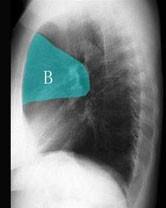

在图所示正常胸部X线影像图像上,该英文字母所代表的肺段为 ( )A、舌叶上段B、前段C、后段D、尖后段E、尖段

问题 在图所示正常胸部X线影像图像上,该英文字母所代表的肺段为 ( )

选项 A、舌叶上段 B、前段 C、后段 D、尖后段 E、尖段

答案 B